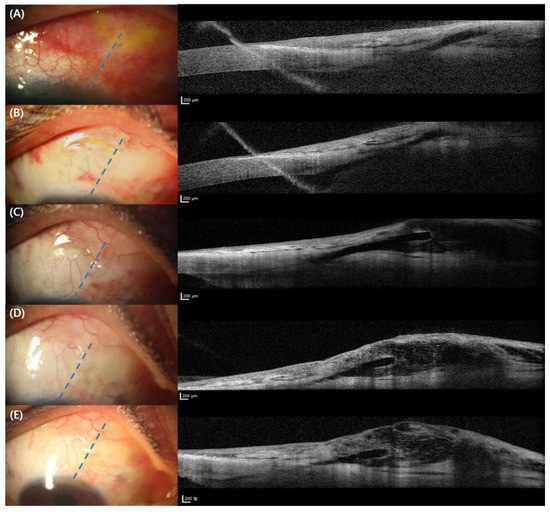

Surgical procedures were performed by a skilled surgeon (S.R.) as described elsewhere [4]. Briefly, after topical anesthesia, air and ocular viscoelastics were injected into subconjunctival space to dissect the conjunctiva and the tenon’s capsule to confirm the presence of the mobile conjunctiva. Almost the entire conjunctiva was immobile due to adhesion (Figure 2A), but fortunately, some spared mobile conjunctiva was noted (Figure 2B) in the superonasal quadrant. A 0.05 mL mix of 2% lidocaine with epinephrine (1:10,000, 0.1 mL) was injected using a 30 G needle into the superior subconjunctival space located approximately 6 mm apart from the region that the XEN tip is expected to occupy. After an injection of viscoelastics to maintain the anterior chamber using a 1 mm side port, the XEN injector was advanced through a 1.5 mm clear corneal incision at the inferotemporal limbus toward the opposite superonasal target angle The injector was approached to the angle into the subconjunctival space 2 mm apart from the limbus. After confirming the allocation of the XEN gel stent in the mobile conjunctiva by the dissection described earlier, the injector was moved backwards and removed gently out of the corneal incision. The proper location and length (approximately 1 mm) of the stent in the anterior chamber were checked using a surgical gonioscope, and the mobility and length (approximately 3 mm) of the subconjunctivally located part of the stent were confirmed (Figure 2C,D). Irrigation and aspiration were carried out to remove the viscoelastics. The corneal wounds were secured by hydrosealing using a balanced salt solution. A quantity of 0.05 mL mitomycin C (MMC) 0.4 mg/mL was injected into the superonasal subconjunctival space using a 30 G needle [4].

Figure 2. Intraoperative findings for XEN gel stent under a surgical microscope. (A) Blue arrows indicate immobile conjunctiva due to adhesion. (B) Blue line indicates spared conjunctiva. (C) Blue arrows indicate XEN gel stent. (D) Blue arrow indicates XEN gel stent during gonioscopy examination.